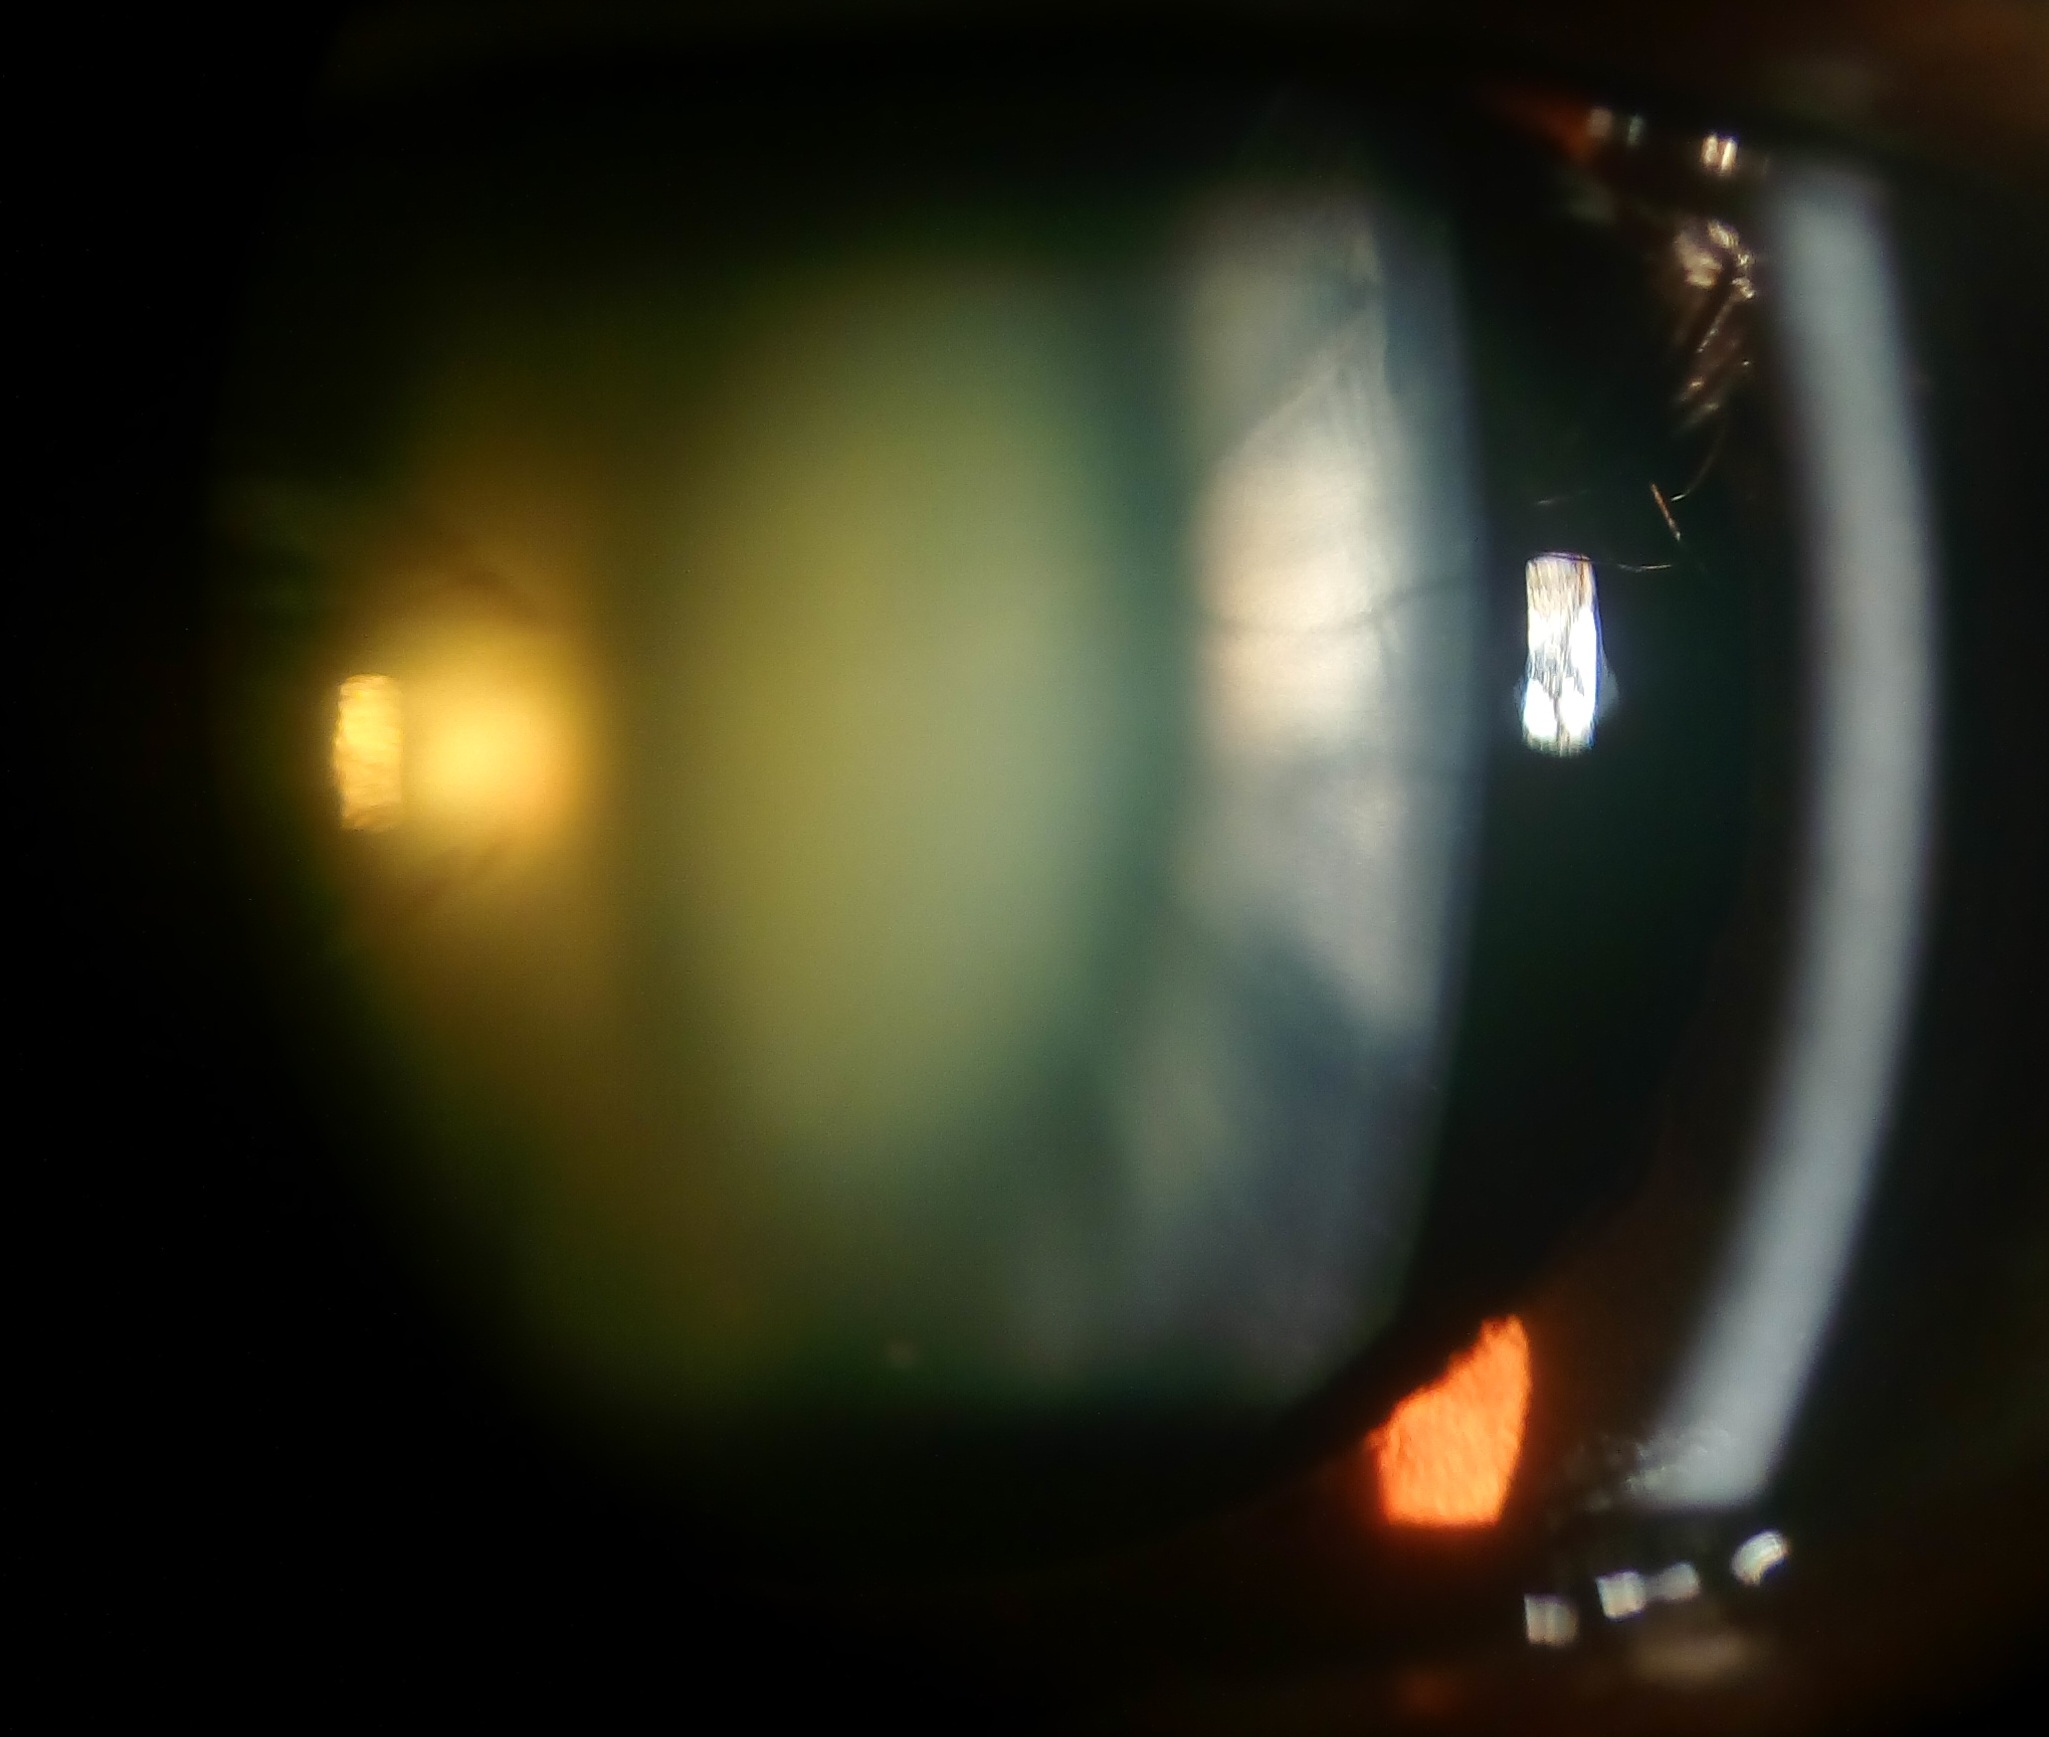

Cortical and nuclear sclerotic cataract. Note opacification of central oval shaped nucleus and surrounding cortex are visible separately by oblique slit beam.

| current | 10:01, June 7, 2017 | 2,049 × 1,737 (542 KB) | Kabir.Hossain (talk | contribs) | Cortical and nuclear sclerotic cataract. Note opacification of central oval shaped nucleus and surrounding cortex are visible separately by oblique slit beam. |